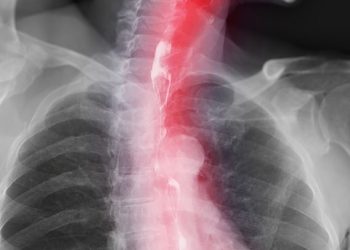

Read moreDetailsPeople with esophageal cancer have a much lower chance of survival than those with other types of cancer. It's important...